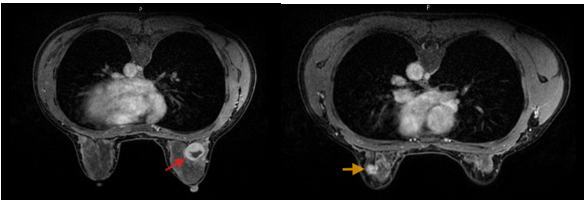

Hình 2. Hình ảnh MRI: Vú phải: Vị trí khoảng 11h, cách núm vú 35mm, có tổn thương dạng nang phức hợp kích thước 26x25x27mm, bờ đều ranh giới rõ, thành dày không đều và ngấm thuốc sau tiêm – BIRADs 4A (mũi tên đỏ). Vú trái: Vị trí khoảng 1h, cách núm vú 45mm có nốt tổn thương kích thước 18x13x9mm, bờ tua gai, co kéo nhẹ nhu mô tuyến vú lân cận; không thấy xâm lấn da và thành ngực – BIRADs 4C (mũi tên vàng).

– Chụp cộng hưởng từ tuyến vú: Hình ảnh tổn thương vú trái (phân loại BIRADS 4C). Tổn thương dạng nang phức hợp vú phải (phân loại BIRADS 4A).